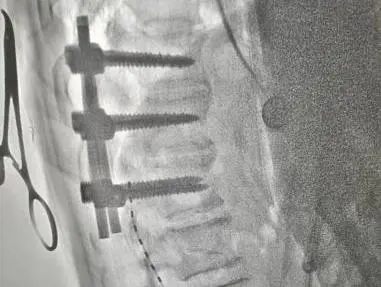

4月27日在医院复合手术室,由寿记新主任医师、管海博主治医师共同完成颈段及腰段短时程脊髓电极植入术,为患者尽早拔除气管套管、完全清醒、站起来、能走路、回归生活奠定了良好基础。

病例二:老年男性,1个月前“因高处坠落致颅脑及胸段脊髓损伤后双下肢截瘫”,由外院转入神经外科一病区,后经积极评估、讨论后给予胸段椎管扩大减压+内固定术。术后虽左下肢可稍活动,但右侧下肢仍无明显活动、大小便排便困难,需持续卧床,家属进行照顾。患者及家属治疗愿望迫切,1周前科室再次充分讨论下一步治疗方案,最后决定行腰段短时程脊髓电刺激手术治疗。